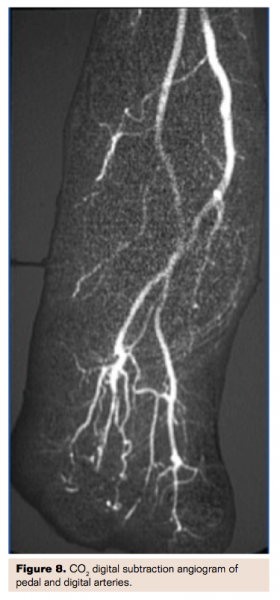

Carbon Dioxide Angiography

Without doubt the best way to avoid contrast nephropathy is simply not to administer any contrast. This has historically been possible using CO2 angiography13 but early systems were somewhat difficult to use, potentially dangerous to patients in the event of a mishap, and required use of large, bulky CO2 tanks. More recently, very portable, commercially available systems (Co2mmander, Portable Medical Devices) have been developed in which a very small canister of liquid carbon dioxide allows instantaneous conversion of liquid to gaseous CO2 that is easily administered using a double syringe system with a four-way stopcock (Figure 4). Many centers have adopted this system with highly satisfactory results and no patient safety issues. Angiographic images are of high quality for large vessels including aortoiliac studies as well as vessels as small as tibial and even pedal vessels (Figures 5-8). Placement of catheters as distally as possible in the circulation allows optimal imaging of smaller, distal vessels. Angiographic visualization has proven adequate for interventional procedures as well. The risk of contrast nephropathy is virtually zero, the cost of CO2 is extremely low, and there is no risk of contrast allergy further enhancing the safety profile of this approach.